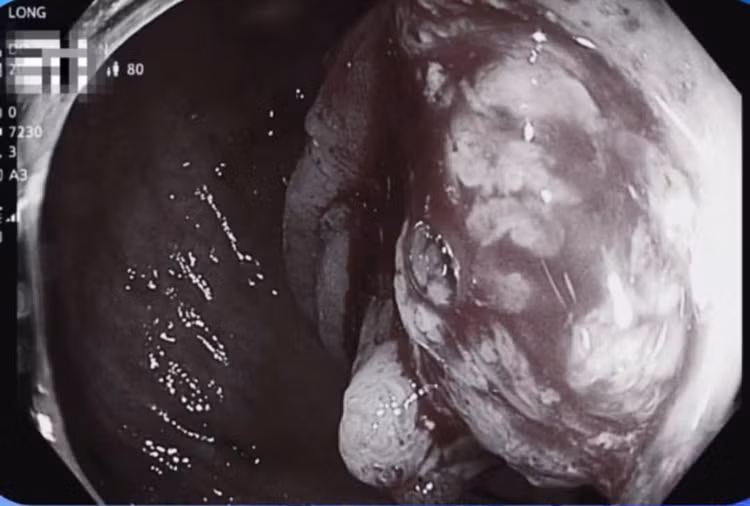

Bệnh nhân được chỉ định chụp CT ổ bụng và nội soi đại tràng. Kết quả chụp CT ổ bụng ghi nhận hình ảnh theo dõi u đại tràng sigma, có hạch lân cận, tổn thương tiêu xương thân đốt sống L3 (hướng tới tổn thương thứ phát) và nốt nhỏ tuyến thượng thận phải.

Kết quả nội soi đại tràng phát hiện đoạn cuối đại tràng có khối sùi loét, bề mặt nham nhở, dễ chảy máu, chiếm gần hết chu vi lòng trực tràng. Bác sĩ tiến hành sinh thiết làm xét nghiệm mô bệnh học, kết quả Carcinoma tuyến biệt hóa vừa, xâm nhập.

Dựa trên cơ sở các xét nghiệm, chẩn đoán hình ảnh và thăm dò chức năng đã thực hiện, bác sĩ chẩn đoán bệnh nhân mắc ung thư đại tràng sigma, phân độ T3N1M1 (giai đoạn muộn đã di căn).